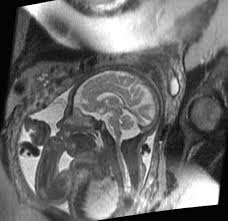

02. Fetal MRI – A non-invasive imaging technique that provides a more detailed view of the fetal brain, often used in complex cases when the diagnosis is not clear on ultrasound.